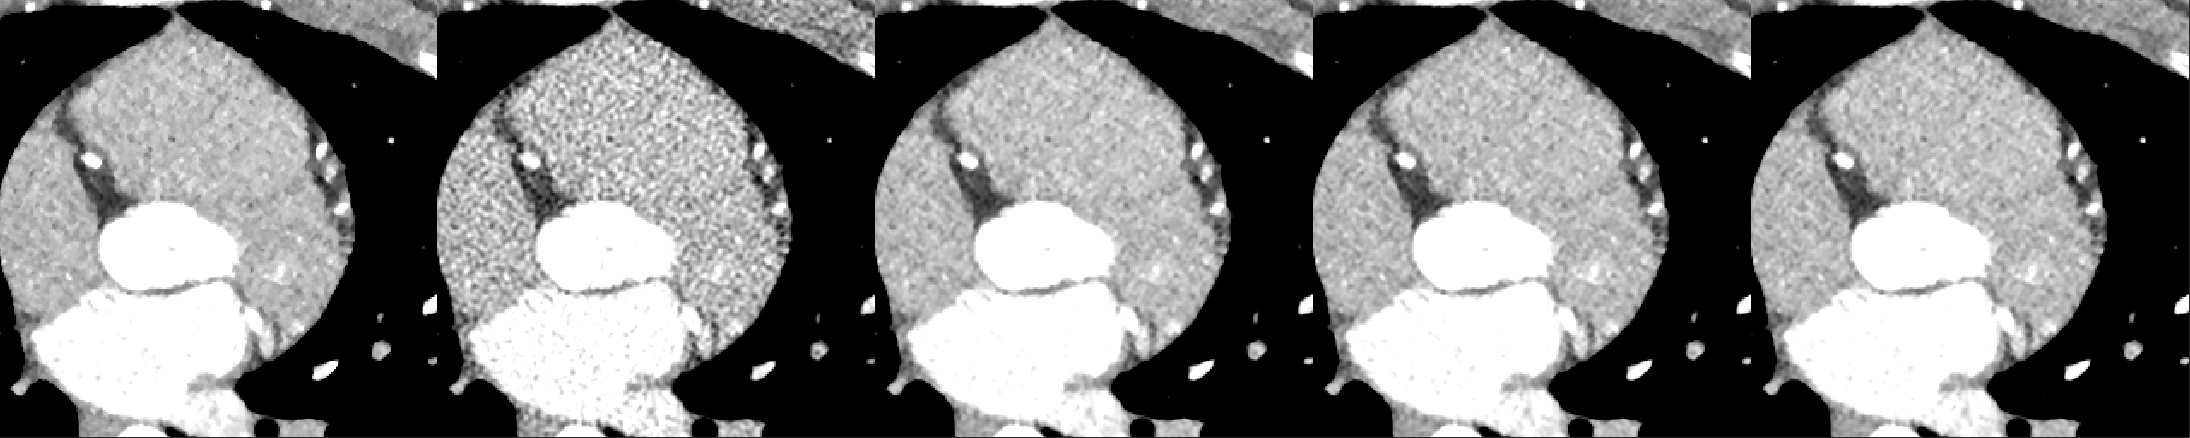

A cardiac FBP image was inferenced on the trained DL-MBIR network. Inference time for every network was between 4 and 6 seconds, and it goes up with the increase in the number of input channels. The MBIR version of the same exam was also available. Figure 3 shows a comparison, for 4 slices – LABEL:sub@fig:Image_10, LABEL:sub@fig:Image_50, LABEL:sub@fig:Image_90, and LABEL:sub@fig:Image_170 in the image volume, among MBIR image, FBP image, and the outputs of DL-MBIRZ𝐷𝐿-𝑀𝐵𝐼subscript𝑅𝑍DL\text{-}MBIR_{Z}, where Z=1, 3, 5𝑍135Z=1,\ 3,\ 5. Figure 4 shows a comparison, for the same slices in the image volume, among difference between images and the MBIR images. Figure 5 has a profile plot to show the comparison of DL-MBIRZ𝐷𝐿-𝑀𝐵𝐼subscript𝑅𝑍DL\text{-}MBIR_{Z} and FBP images w.r.t the MBIR images.

Figure 3: Reconstructed image. (left to right): MBIR𝑀𝐵𝐼𝑅MBIR, FBP𝐹𝐵𝑃FBP, DL-MBIR1𝐷𝐿-𝑀𝐵𝐼subscript𝑅1DL\text{-}MBIR_{1}, DL-MBIR3𝐷𝐿-𝑀𝐵𝐼subscript𝑅3DL\text{-}MBIR_{3}, DL-MBIR5𝐷𝐿-𝑀𝐵𝐼subscript𝑅5DL\text{-}MBIR_{5}. LABEL:sub@fig:Image_10, LABEL:sub@fig:Image_50, LABEL:sub@fig:Image_90 and LABEL:sub@fig:Image_170 represent different slices in the image volume. WW/WL 450/0 HU.

Visually, all DL-MBIR images bear close resemblance to the MBIR images in figure 3. It is confirmed by the difference images in figure 4. In the profile plot of Figure 5, the DL-MBIR profiles closely follow that of MBIR.